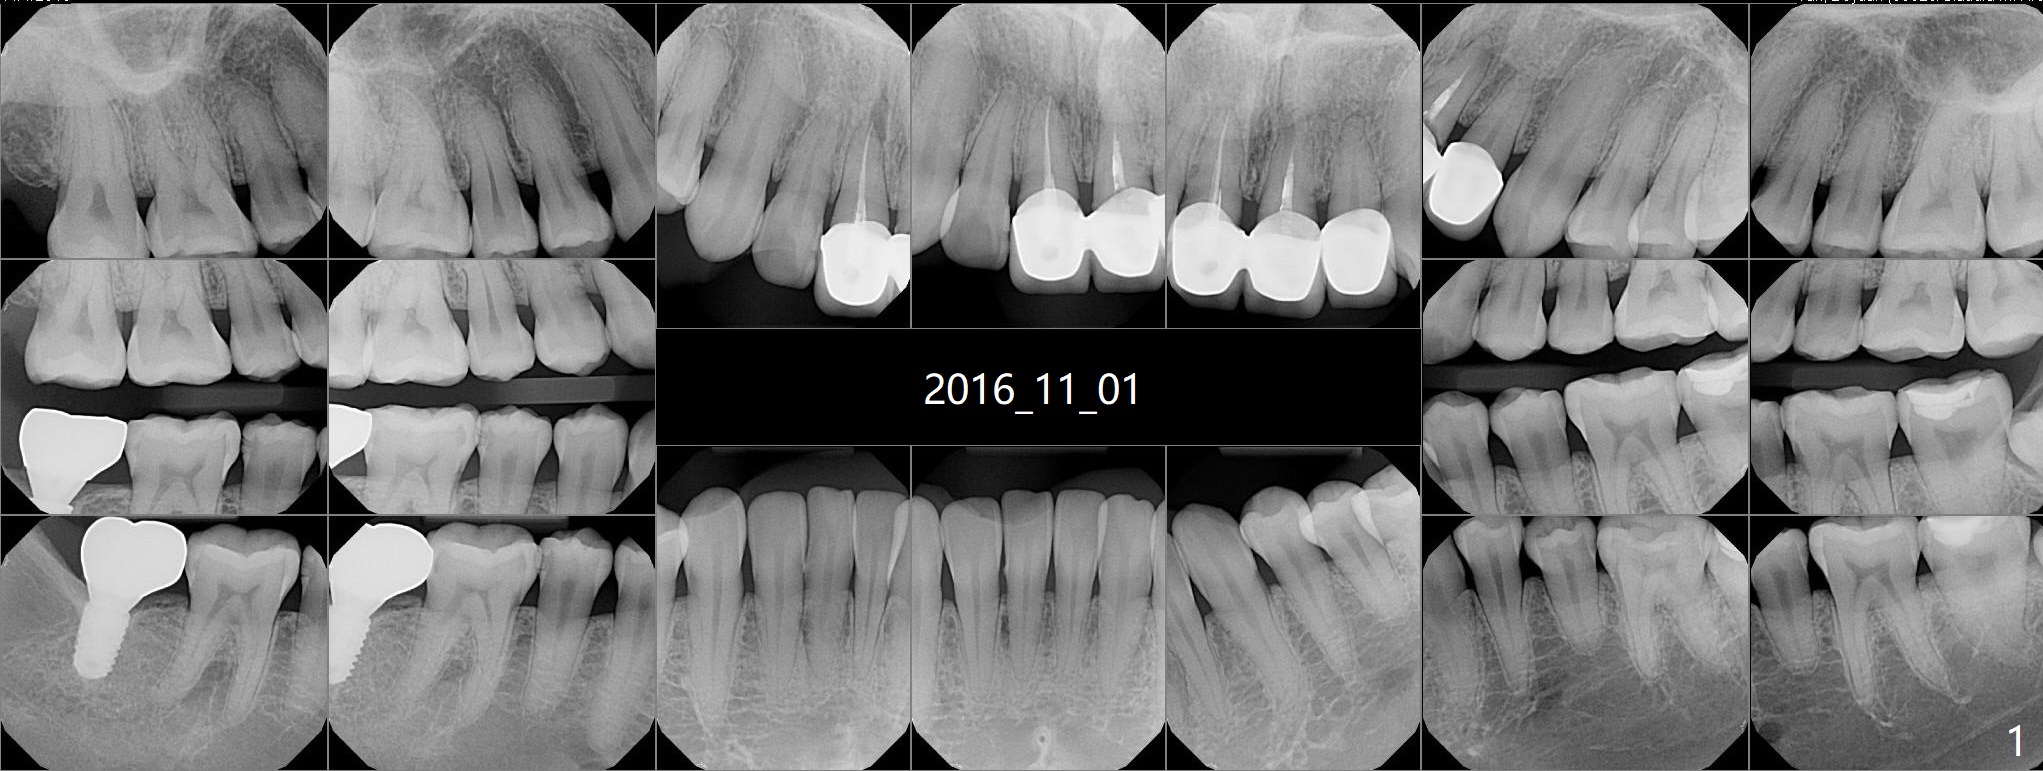

Loose FPD A 29-year-old woman has multiple restoration (Fig.1). Recently the upper anterior bridge is loose. It appears that there is breakage between #9 and 10 and that the tooth #9 is non-salvageable (Fig.2). The FPD will be sectioned between #8 and 9. It is possible that the tooth #8 is non-salvageable. Since the bone height is not ample, an implant system with high stability will be chosen for this case. Osteotomy will be established slightly distal to avoid the Incisive Canal. Photos will be taken preop. Do not forget the Planning Kit; angled abutment may be used. Return to